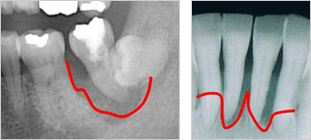

- 1位歯周病

- 歯を支える骨がなくなり、グラグラになる

- 噛むと痛く、しっかりと噛めない

- 歯茎が腫れ、膿が出てくる

これらの症状は、状態がひどくなるまで現れない場合が多い。